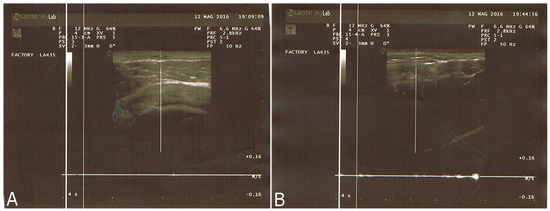

2.2.1. Breast Fat Grafting

2.2.2. Pathological Scar Fat Grafting